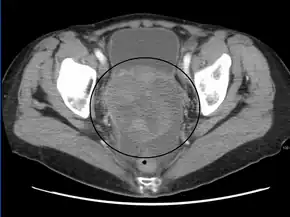

The preliminary diagnosis begins with a pelvic examination, serum tumor marker test and imaging. Physicians may feel a large palpable mass or lump in lower abdomen upon insertion of the gloved fingers into the vagina. To further identify the histologic subtypes of OGMTs, blood samples of patients are collected to analyse the serum level of biomarkers released by the tumor cells. A surge in the plasma levels of human chorionic gonadotropin and alpha-fetoprotein is indicative of OGMTs.[1] Lactate dehydrogenase, alkaline phosphatase and cancer antigen 125 might potentially increase as well.[24] To visualize the location and morphology of the tumor, transvaginal ultrasonography is usually employed.[1] The most characteristic appearance is a parenchymal-like heteroechoic mass with sharp borders and high vascularization.[1] Computed tomography would produce stacked image inside the peritoneal region of the body to visualise the lobular pattern of the tumour.[1] Usually for dysgerminoma, solid mass being compartmentalized into lobules with enhancing septa may be evident for haemorrhage or necrosis.[1]